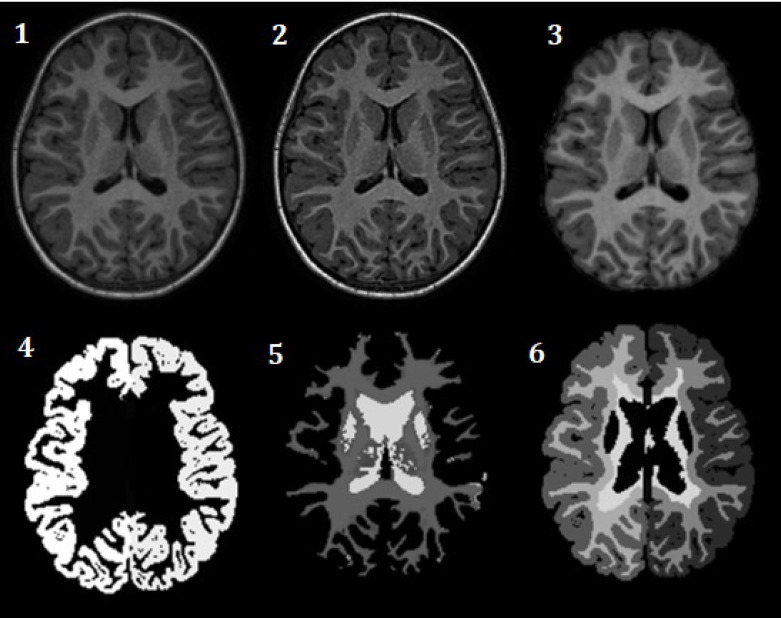

Materials & methods: Surface-based and volume-based features were extracted from FS software and CAT12 toolbox for Statistical Parametric Mapping (SPM) software to estimate ROI-wise biomarkers. These biomarkers were compared between 18 males Typically Developing Controls (TDCs) and 40 male subjects with ASD to assess group differences for each method. Finally, agreement and regression analyses were performed between the two methods for TDCs and ASD groups.

Abstract Image